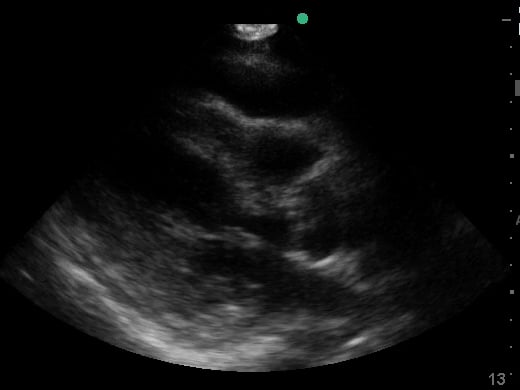

Pericardial effusion in cardiac ultrasound refers to an abnormal accumulation of fluid within the pericardial sac, the double-layered membrane surrounding the heart. This condition can impede the heart’s ability to fill and pump blood effectively, potentially leading to cardiac tamponade, a life-threatening emergency. Early detection through echocardiography is crucial for timely medical intervention and improved patient outcomes.

Utilizing medical ultrasound, healthcare professionals can accurately identify and quantify pericardial effusions, assessing their size, location, and hemodynamic impact. Ultrasound imaging provides real-time visualization of the fluid build-up, enabling precise diagnosis and guiding potential therapeutic procedures such as pericardiocentesis. This non-invasive technique is indispensable for managing cardiac health and preventing severe complications.